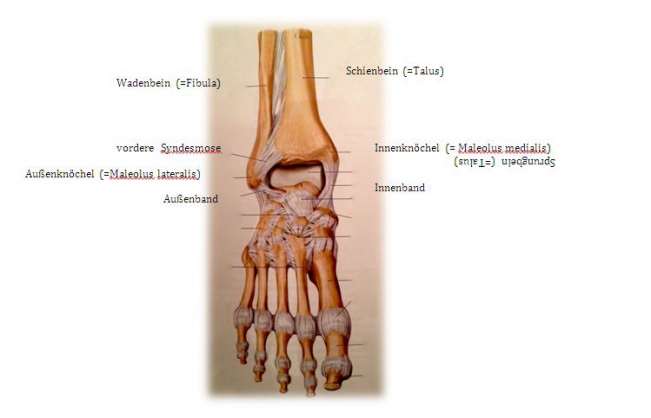

undefined

Fig.1) Anatomy of the upper ankle joint (from: Prometheus ®, MLP)